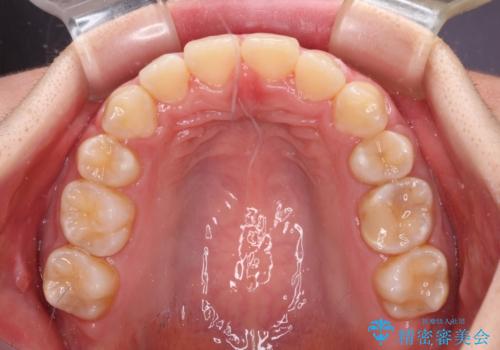

- 上の前歯の出っ歯とでこぼこの歯並びを気にして来院された患者様です。

口元を積極的に引っ込めるために、上下左右の小臼歯4本を抜歯することとしました。